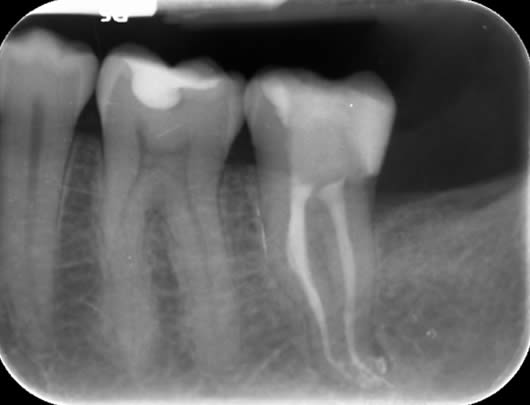

Case 3: Root canal treatment – narrow canals.

As a tooth ages, whether prematurely following trauma or long-term irritation, or in accordance with natural ageing, the root canals can become narrower due to the laying down of further dentine (tooth structure). This can make the canals difficult to locate and very challenging to negotiate to full length. As with finding the elusive MB2 canal (Case 2), we use our experience and the use of the dental microscope to conservatively remove tooth tissue in just the right areas to locate these canals. This cases shows a tooth (UL6) in which it is difficult to see the canals on the radiograph as they are very narrow. We were able to locate four canals (including the challenging MB2 canal) and prepare and fill them.

Before treatment UR6

Following root canal treatment UR6